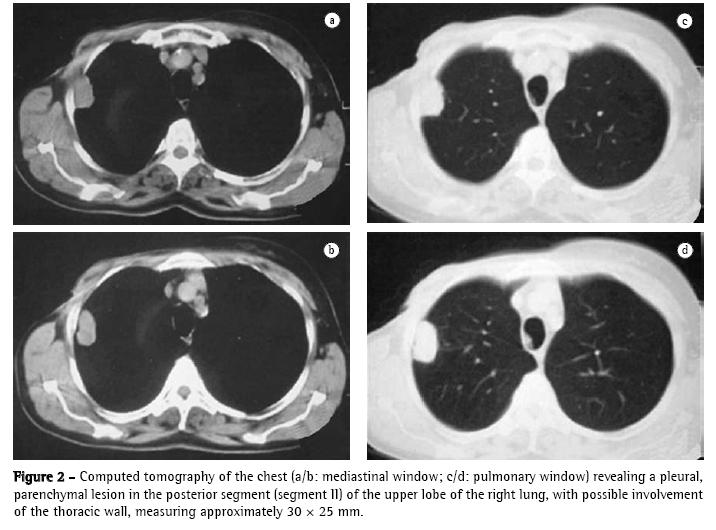

A 60-year-old Caucasian female who had been in menopause for 14 years was referred to the Department of Oncology due to the presence of a pulmonary nodule on chest X-ray (Figure 1) diagnosed in the postoperative follow-up evaluation of breast cancer.

The patient then underwent computed tomography of the chest, which revealed a pleural, parenchymal pulmonary nodule measuring approximately 30 × 25 mm (Figure 2) in the right lung. Therefore, a hypothetical diagnosis of pulmonary metastasis of the breast carcinoma previously removed was made, and biopsy was indicated for diagnostic confirmation.